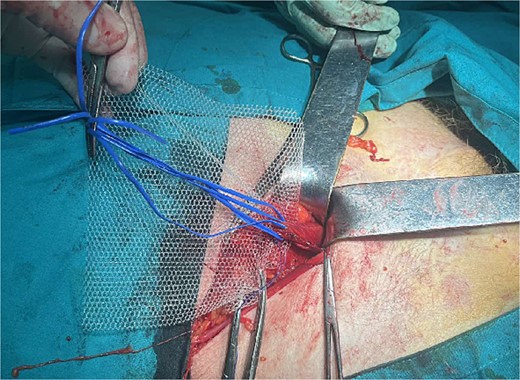

A 72-year-old patient, in good physical condition with a BMI of 26.1, came for an examination due to swelling in the right lateral abdominal wall without swelling of the scrotum. The patient was operated on for a right-sided inguinal hernia as an 8-year-old boy, but there was no appropriate medical documentation for the operative technique used. A month ago, besides the swelling, he experienced occasional abdominal pain and difficulties during physical activities in his garden. During clinical examination, a soft swelling in the right lateral abdominal wall, compressible under palpation was ascertained (Fig. 1). The abdominal ultrasound and contrast abdominal CT showed a thinned right abdominal wall with superficial intestinal loops and the differential diagnosis of a large recurrent inguinal or Spigelian hernia was presumed (Fig. 2). The patient received one dose of prophylactic cephalosporin preoperatively, and was operated on under general endotracheal anesthesia, in a supine position with a lumbar pillow placed for a slight tilt to the left. A right lateral lumbar-inguinal skin incision 4–5 cm above the anterior superior iliac spine in a horizontal direction following the lumbar dermatomal lines was performed. Subcutaneous fat was gently separated and the hernial sac dissection went to its apex below the right costal arch and base to the deep inguinal opening. When the sac was completely freed, the final diagnosis of giant recurrent indirect inguinal hernia (Fig. 3), and the sac with its content was repositioned in the abdominal cavity without opening the abdominal cavity and partial closure of the internal iliac ring was performed with resorptive sutures. After the dissection of the inguinal ligament up to the pubic tubercle (without extending the skin incision) a 15 × 12 cm polypropylene mesh was placed (Fig. 4), fixed to the pubic tuberculum and conjoint tendon with a laparoscopic taker (Fig. 5), and the ileopubic ligament partly with individual and partly with continuous non-absorbable polypropylene 2/0 suture. An opening for the spermatic cord was provided and medially the mesh was fixed with individual resorptive stitches (Fig. 6). The aponeurosis of the external oblique muscle was closed as much as it allowed to be approximated followed by individual subcutaneous and skin stitches (Fig. 7). The operating time was 65 minutes without blood loss and the patient had a quick and satisfactory recovery. He was discharged from the hospital on the third post-op day, and the skin stitches were removed on the 14th day. One month after the surgical treatment the patient was in good condition without any complaints (Fig. 8).

Placement of the polypropylene mesh 15 × 12 cm after dissection of the spermatic cord

Mesh fixation to the pubic tuberculum and conjoint tendon with a laparoscopic taker

In the presented case, the decision was made for an open approach, due to the presence of a giant hernia, with uncertainty as to whether it was a Spigelian or recurrent inguinal hernia. During the surgical procedure, all recommendations were applied: dissection and non-resection of the hernial sac, and placement of a mesh with wide openings in the appropriate size (15 × 12 cm) [7]. The mesh was placed in the desired locations (pubic tuberculum, conjoint tendon) using a laparoscopic taker to avoid skin incision extension caudally and maneuver in the small inguinal space. Resorbable sutures were used to fix the mesh above Hesselbach's triangle to prevent inguinodynia, the most frequent postoperative complication [3, 4]. Even though, drainage should be placed in giant hernias, where a greater portion of the subcutaneous or musculoaponeurotic areas is dissected [8], in the presented case, the careful and precise dissection and adequate hemostasis without any bleeding led to the decision not to put drainage. Single sutures were placed to minimize the free spaces between the subcutaneous tissue and the aponeurosis. Also, following recommendations a prophylactic single-dose cephalosporin antibiotic was given, half an hour before the start of the intervention [9]. Postoperative outcomes are good when following the surgical anatomy of the inguinal region and the surrounding anatomical regions, meticulous surgical technique, proper hemostasis, and mesh placement technique [10].